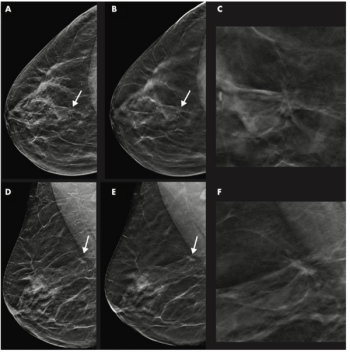

Implementing artificial intelligence tools with breast imaging can pinpoint overlooked interval cancers and decrease provider workload in screening mammography programs.

Not only did this combination improve breast cancer detection, but it could also catch more potentially invasive cancers earlier.

MRI catches more malignant lesions in women with dense breasts who undergo digital breast tomosynthesis than those who have digital mammography alone.